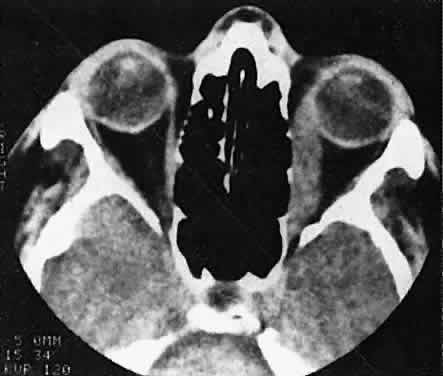

of the globe. CT scans show the topography of the orbital mass (Fig. 1A), as well as the possible extension into adjacent bone, paranasal sinuses, or

the intracranial cavity. The circumscription that may be noted

on CT is relative, because the lesion is not encapsulated and microscopically

infiltrates normal tissue. Echography shows internal echoes of

low-to-medium amplitude. Because the cellular tumor absorbs acoustic

energy, the amplitude of the spikes falls off somewhat through the lesion (see Fig. 1B and C). MRI can help define the tumor's relationship to extraocular muscles (Fig. 2).  Fig. 1. A. Proptosis and downward, outward globe displacement developed over 2 days

in a 3-year-old girl. A homogeneous mass fills the superomedial orbit. B. Contact B-scanning shows a relatively well-circumscribed mass with uniform

internal echoes. C. Contact A-scanning shows the internal reflectivity to be of low to medium

amplitude, consistent with a sarcomatous lesion. Biopsy results confirmed

the diagnosis of rhabdomyosarcoma. Fig. 1. A. Proptosis and downward, outward globe displacement developed over 2 days

in a 3-year-old girl. A homogeneous mass fills the superomedial orbit. B. Contact B-scanning shows a relatively well-circumscribed mass with uniform

internal echoes. C. Contact A-scanning shows the internal reflectivity to be of low to medium

amplitude, consistent with a sarcomatous lesion. Biopsy results confirmed

the diagnosis of rhabdomyosarcoma.